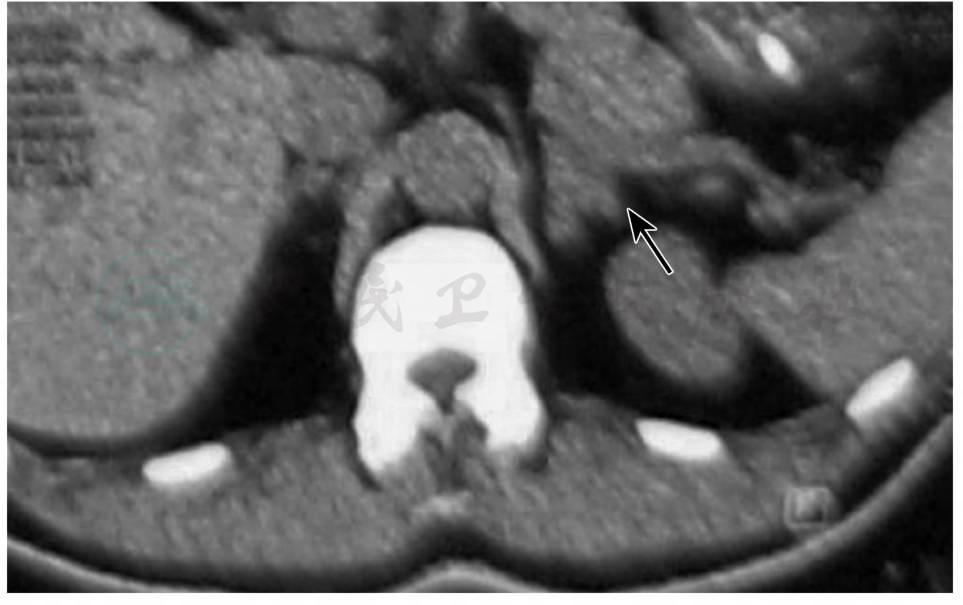

9.肾上腺CT检查(2010年7月10日)

左侧肾上腺分叶状占位,可能为腺瘤(图3)。

图3 肾上腺CT(2010年7月10日)检查:示左侧肾上腺分叶状占位,可能为腺瘤(箭头)